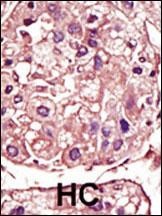

Anti-TGFBR1 / ALK5 antibody IHC staining of human small intestine. Immunohistochemistry of formalin-fixed, paraffin-embedded tissue after heat-induced antigen retrieval.